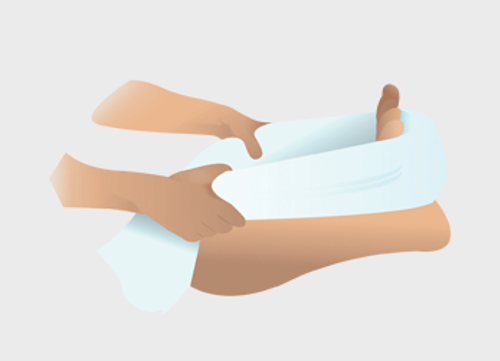

Hoe u de rekoefening voor de peesplaat uitvoert:

- Rol een handdoek op en pak de 2 uiteindes met uw handen vast (zoals op de afbeelding).

- Plaats de handdoek onder uw pijnlijke voet.

- Rek de peesplaat door uw tenen naar u toe te trekken.

- Houd dit 20 tot 30 seconden vast.